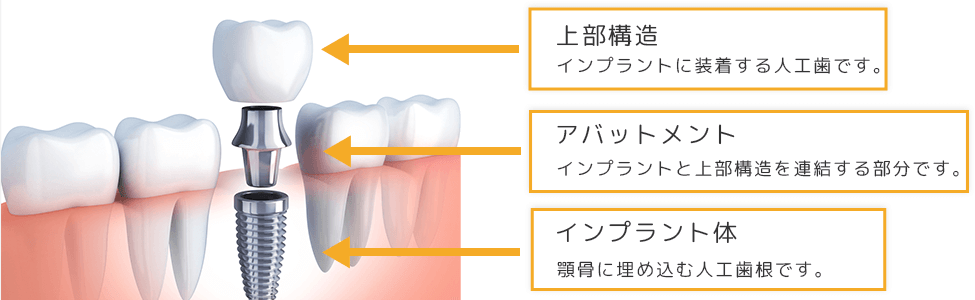

インプラントは、失われた歯の代わりに人工歯根を埋め込み、人工歯を装着して歯の機能を補う治療法です。

現存している健康な歯を削ることなく、天然歯のように自然な見た目で噛む力も同程度に回復することができます。

患者様のご要望をお伺いし、丁寧なカウンセリングを行います。

その後歯科用CTで撮影した3D画像を用いた精密診査を行い、検査結果を元に患者様のご希望にできるだけ沿える綿密な治療計画を立案します。

痛みを感じないよう局所麻酔を行い、埋入手術を行います。

その後、インプラントと骨が結合するまで約3~6か月程度の経過観察を行います。

むし歯や歯周病がある場合は治療を行い、症状が安定した状態になったら治療を進めます。

患者様に合った人工歯を作製し、骨とインプラントがしっかり結合したら、装着して治療は完了です。

インプラントを長持ちさせるためには、口腔内を常に清潔に保つことが大切です。 日々のお手入れに加え、定期的な検診を受けていただき、インプラントや人工歯の状態、咬み合わせ具合を確認し、メインテナンスを行う必要がございます。

| インプラント1本あたり | 220,000円~330,000円(税込) |